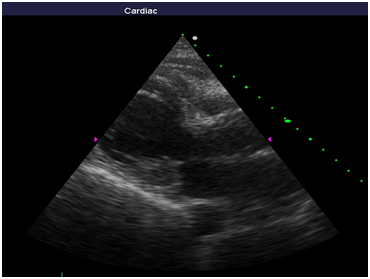

Repeated echocardiography revealed the zone of violation of local contractility (akinesis and pronounced hypokinesis) all segments on the medial and apical level with the formation of acute left ventricular aneurysm, a marked reduction of EF (23%), hyperkinesis all segments at the basal level (Figure 4-8). Troponin test was strongly positive (Figure 9). The patient is re-examined by a cardiologist, on the basis of ECG, Echo pattern, and the presence of markers of myocardial damage diagnosed with acute myocardial infarction in type 2 complicated by development of acute left ventricular aneurysm, acute heart failure Killip class IV. We carried out differential diagnosis between stress cardiomyopathy and myocarditis.

Figure 4 Echocardiography: PLAX, hyperkinesis of the basal segments with apical ballooning.